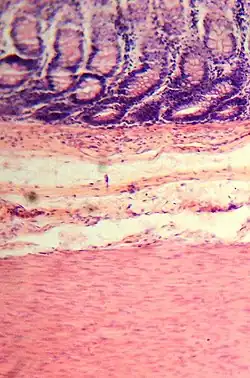

Histología del intestino grueso

Presenta criptas de Lieberkühn, no tiene vellosidades ni pliegues circulares.[44]

En el intestino grueso hay una gran cantidad de exocrinocitos caliciformes. Las poblaciones celulares epiteliales son las mismas del intestino delgado.[45][46]

La diferencia más obvia con el intestino delgado es que es más ancho y que presenta una capa muscular longitudinal que se reduce a tres estructuras en forma de correa, de unos 5 milímetros de anchura, conocidas como taeniae coli, que empiezan en la base del apéndice y se extienden desde el ciego hasta el recto.[2] La capa mucosa de su pared está formada por epitelio columnar simple y, en vez de tener las vellosidades del intestino delgado, el intestino grueso presenta criptas intestinales.[3] A pesar de que los dos intestinos tienen células en forma de cáliz, al intestino grueso son más numerosas. La serosa externa es otra capa de tejido conectivo muy delgada que se continúa focalmente con el peritoneo.